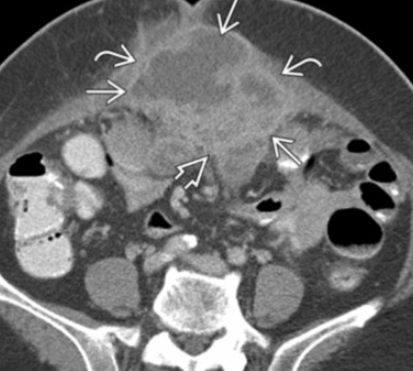

• CT A&P is preferred first test for staging

• MRI is degraded by bowel peristalsis motion and therefore is not preferred

Leiomyosarcoma

• Look for an enlarging uterine mass/uterus with internal areas of hemorrhage/necrosis

• May look largely cystic with blood and shit in there

• Look for mets

• If none seen, should include degenerative/degenerating fibroid in ddx